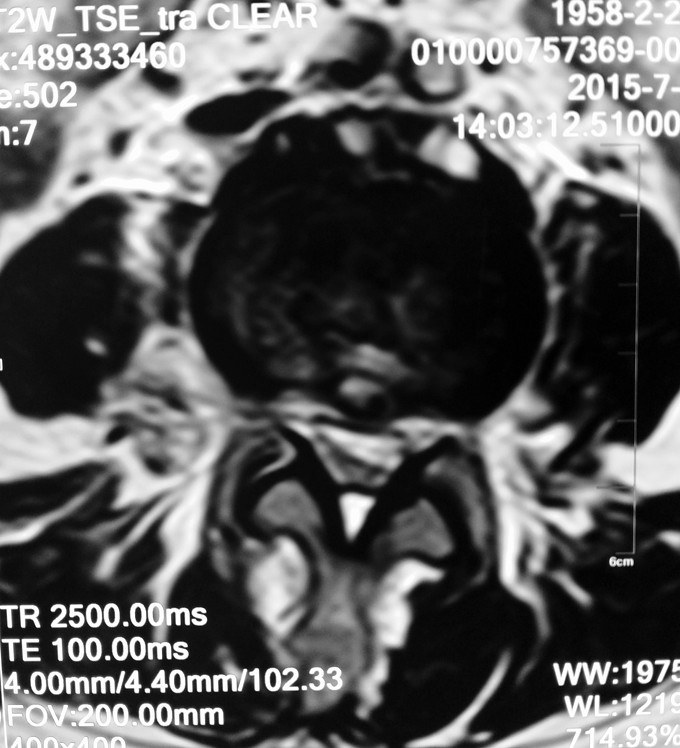

患者女性,58岁。 腰痛间断性发作2年,加重伴左下肢疼痛不适4月 疼痛以久坐和劳累后症状明显,近4月上述症状加重,伴有左下肢麻木疼痛感,经卧床休息后不能缓解。

腰3-4/4-5间隙及椎板压痛及叩击痛,无明显下肢放射痛。左大腿前外侧及膝以下感觉有减退,左侧髋、膝肌力5级,拇趾背伸肌力4级,肌张力不高,左下肢直腿抬高试验40°阳性,加强试验阳性。右下肢感觉肌力正常。 血沉 99mm/h C反应蛋白:4.1ng/L 斑点试验:抗A 111,kangB 127

1.腰3-4结核 2.腰4-5椎管狭窄 因术前血沉比较高,所以予以HREZS抗痨治疗2周,血沉至44mm/h,患者一般情况较前好转。安排手术治疗:后路腰3-4椎间病灶清除椎板植骨+腰4-5减压植骨内固定融合术。

此患者腰椎结核伴有相邻节段椎管狭窄,所以兼有两者的症状。对于此病例我们考虑因患者椎体前方脓肿不明显,所以考虑一起行后方椎间隙病灶清除,植入自体椎板骨融合内固定,同时进行腰4-5后路减压内固定融合术。 不知大家对结核的病人一般是通过何种方式进行病灶清除的?选择原则是什么?